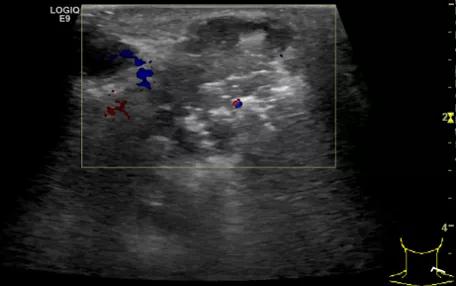

第四例是胸腺癌化妆包,术后、化疗之后淋巴结转移,肿块范围巨大,99mm*61mm,边界不清,呈浸润状,肿块包绕颈动脉,颈内静脉压闭,症状明显。由于患者放化疗也不敏感、血供非常丰富,于是采取多点姑息性消融。姑息性消融后未实现完全消融,病灶大片坏死,肿胀疼痛得到明显的缓解,后续患者未再来复查。

(病例4图例)